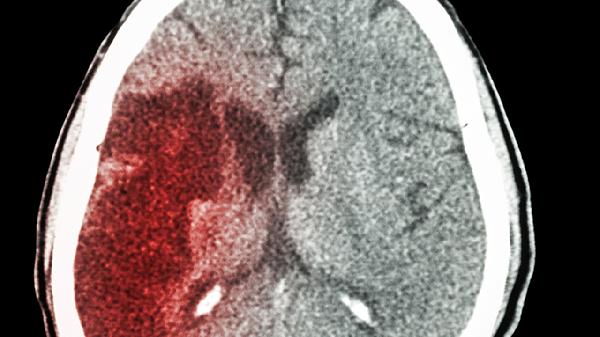

脑出血说话胡言乱语怎么回事

脑出血说话胡言乱语可能由脑组织损伤、颅内压增高、语言中枢受累、代谢紊乱、继发感染等原因引起,可通过药物治疗、手术干预、语言康复训练、控制基础疾病、预防并发症等方式治疗。

脑出血导致局部脑组织受压或坏死时,可能破坏语言中枢神经通路。患者常伴随偏瘫、意识模糊等症状。需紧急使用甘露醇注射液降低颅内压,配合依达拉奉注射液清除自由基,必要时采用开颅血肿清除术。早期介入高压氧治疗有助于改善脑细胞缺氧状态。

血肿占位效应引发颅内高压可导致全脑功能障碍。典型表现包括剧烈头痛、喷射性呕吐。临床常用甘油果糖氯化钠注射液联合呋塞米注射液脱水降压,严重时需行脑室穿刺引流术。监测瞳孔变化和生命体征对判断病情进展至关重要。

当出血累及布罗卡区或韦尼克区时,会出现运动性失语或感觉性失语。患者可能伴随命名障碍、理解困难。治疗需使用胞磷胆碱钠胶囊营养神经,配合长春西汀注射液改善脑循环。发病后2-4周是语言功能康复训练的黄金窗口期。

脑出血患者急性期需绝对卧床,头部抬高15-30度。恢复期饮食宜选择低盐低脂的燕麦粥、蒸蛋羹等软食,避免呛咳。每日进行口面部肌肉训练和简单对话练习,家属应保持耐心沟通。定期复查头颅CT监测血肿吸收情况,控制高血压等基础疾病是预防复发的关键。出现发热或意识状态恶化需立即返院就诊。